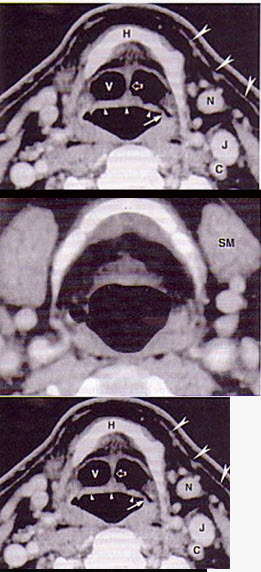

男,55岁,声嘶6年,有长期吸烟史。检查:无呼吸困难。喉镜检查:声带慢性充血,可见右侧声带可见菜花样新生物,右侧声带活动固定,喉部CT检查如下图: 患者术后第二天引流出乳白色液体约500ml,则要考虑()。